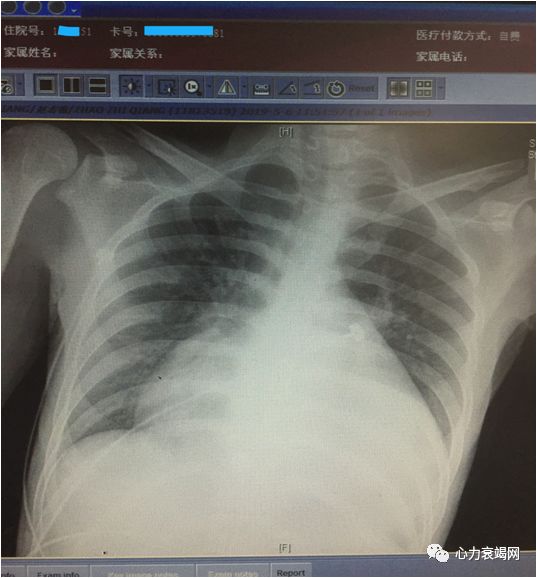

胸片

04

4、影像学依据(心脏彩超、胸片、磁共振)

X线平片:左心增大,主动脉瓣钙化、升主动脉常呈狭窄后扩张